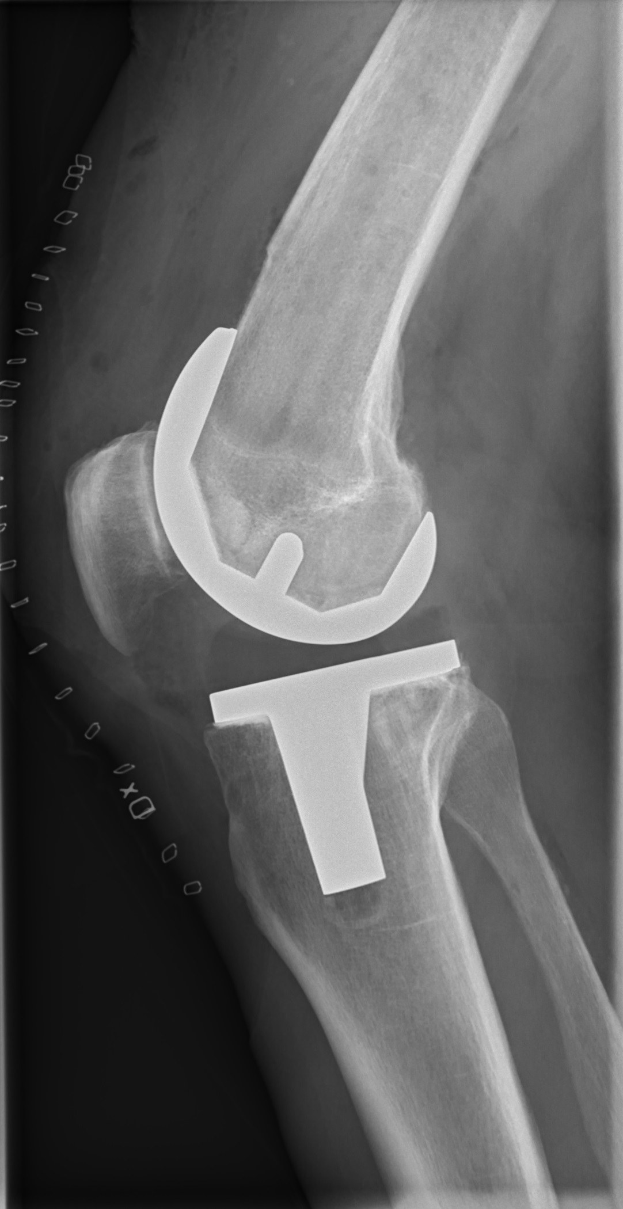

Die Verletzung ereignete sich beim 0:5 (0:5) des SSV Ulm gegen den SC Verl. Spätere Untersuchungen bestätigten einen Riss des vorderen Kreuzbands im linken Knie Davids. Es ist der jüngste in einer Reihe ähnlicher Fälle innerhalb der Mannschaft.